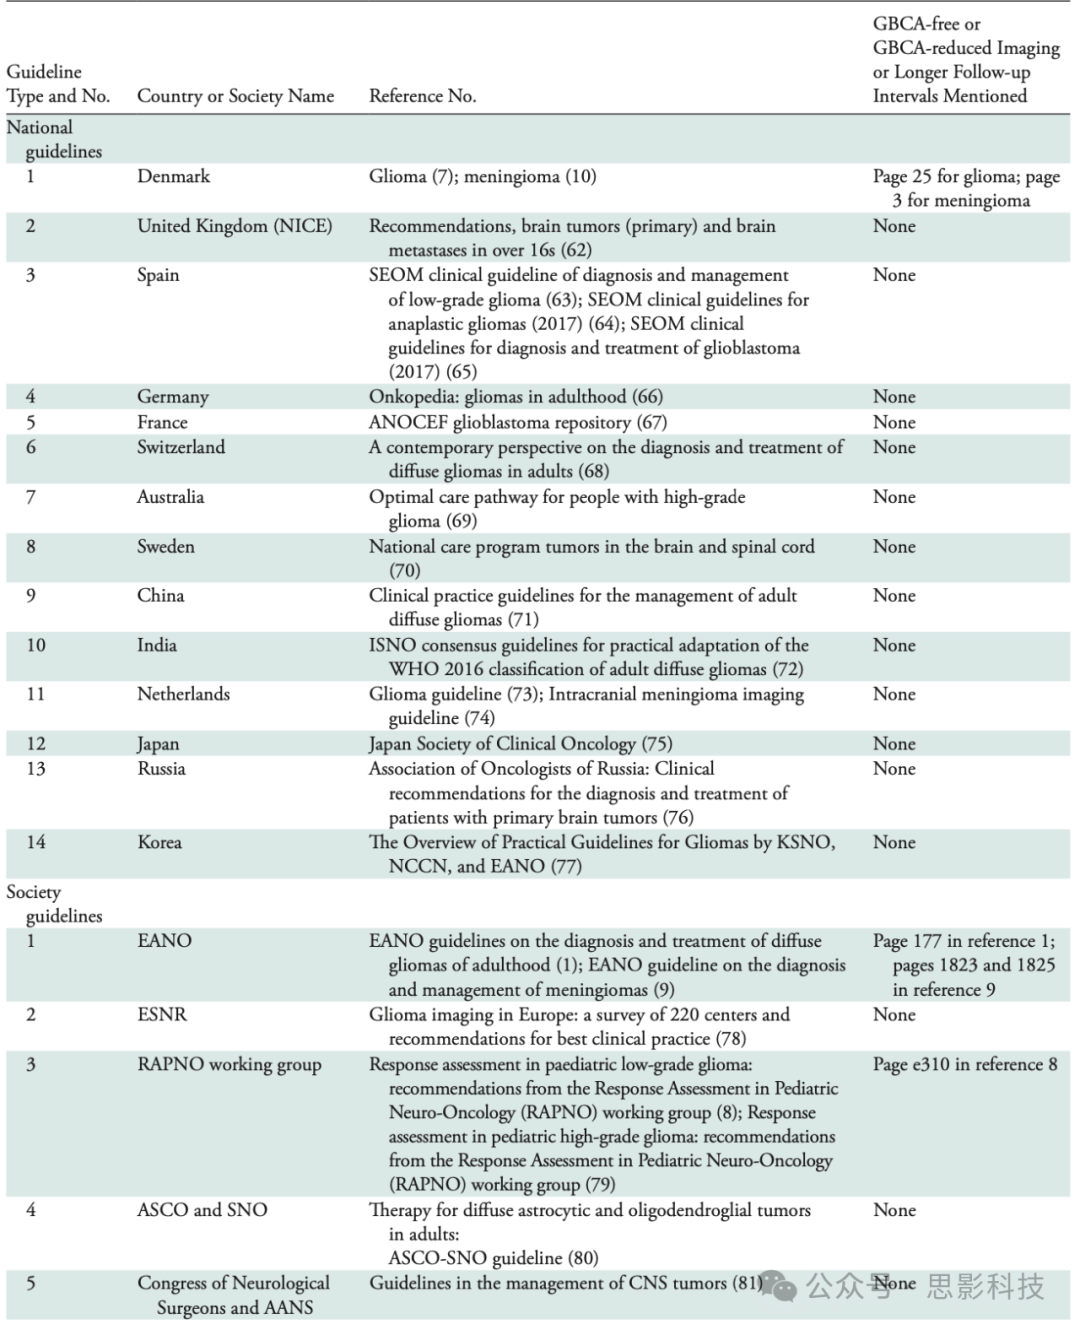

指南综述——我们分析了14个国家和8个国际学会关于儿童和成人胶质瘤和脑膜瘤患者成像实践的指南,旨在尽可能代表所有全球区域(表)。然而,对于一些世界区域和国家,无法追踪到成像指南。在分析的指南中,我们发现支持无GBCA随访或降低扫描频率的证据有限。

表 关于GBCA的指南检查

大多数指南建议在诊断和治疗的所有阶段使用GBCA增强MRI。一些胶质瘤指南提到缺乏关于最佳随访频率的高质量证据(例如,英国国家卫生与护理卓越研究所(NICE)指南;西班牙指南;欧洲神经肿瘤学会(EANO)指南)。EANO指南建议,对于病情稳定的低级别胶质瘤(LGG)(WHO I级或II级)患者,延长随访间隔是合适的,仅在出现新症状时进行额外的MRI检查(1)。NICE指南讨论了频繁扫描随访的可能缺点,如增加患者焦虑和成本。丹麦指南建议对非增强胶质瘤跳过早期术后成像(<48小时),因为评估非增强残留肿瘤有困难,而建议仅在12周后评估切除完整性(7)。儿童神经肿瘤学反应评估指南提出,可考虑在非增强儿童LGG(低级别胶质瘤)中进行无GBCA随访成像(8)。

关于脑膜瘤,EANO和丹麦指南建议对小的无症状脑膜瘤进行无GBCA随访,仅依靠T2加权图像的测量(9,10)。对于WHO I级脑膜瘤,在连续5年每年稳定随访后,MRI间隔也可延长至每两年一次(9,10)。